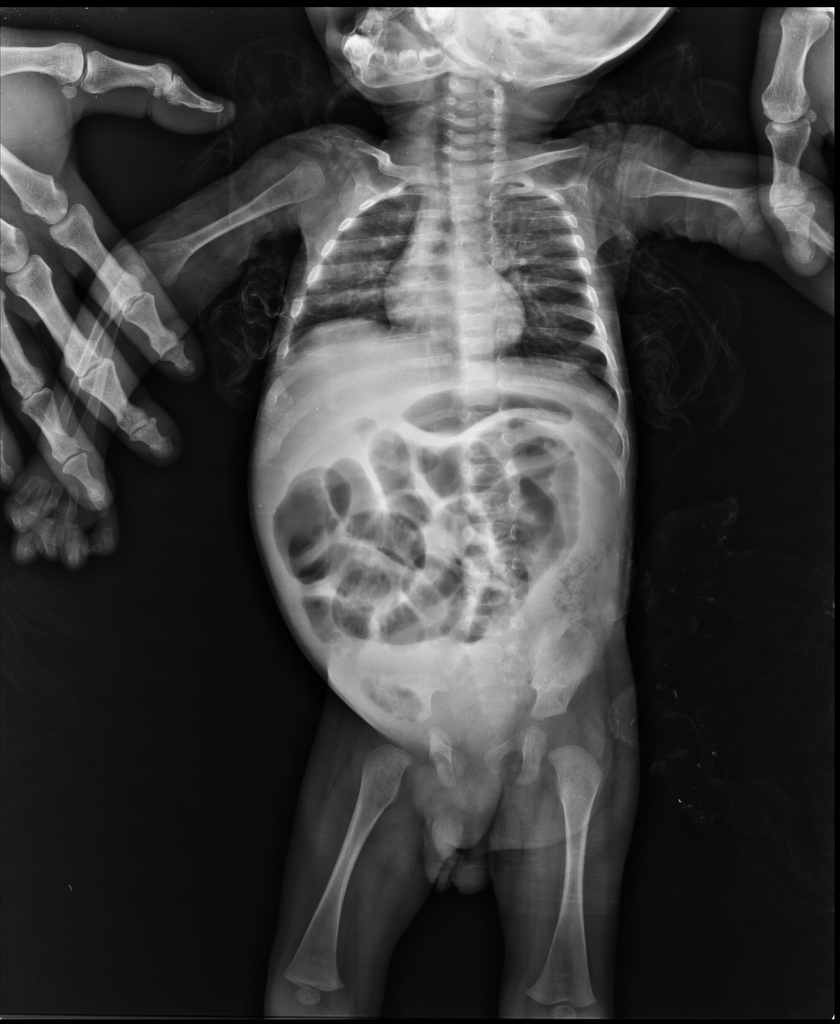

Hirschsprung disease on abdominal radiograph